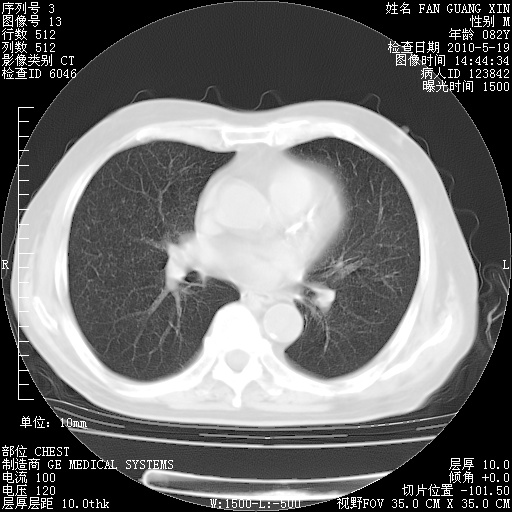

复查肺部CT,明显好转。为什么发热呢?

治疗3周后的肺部CT